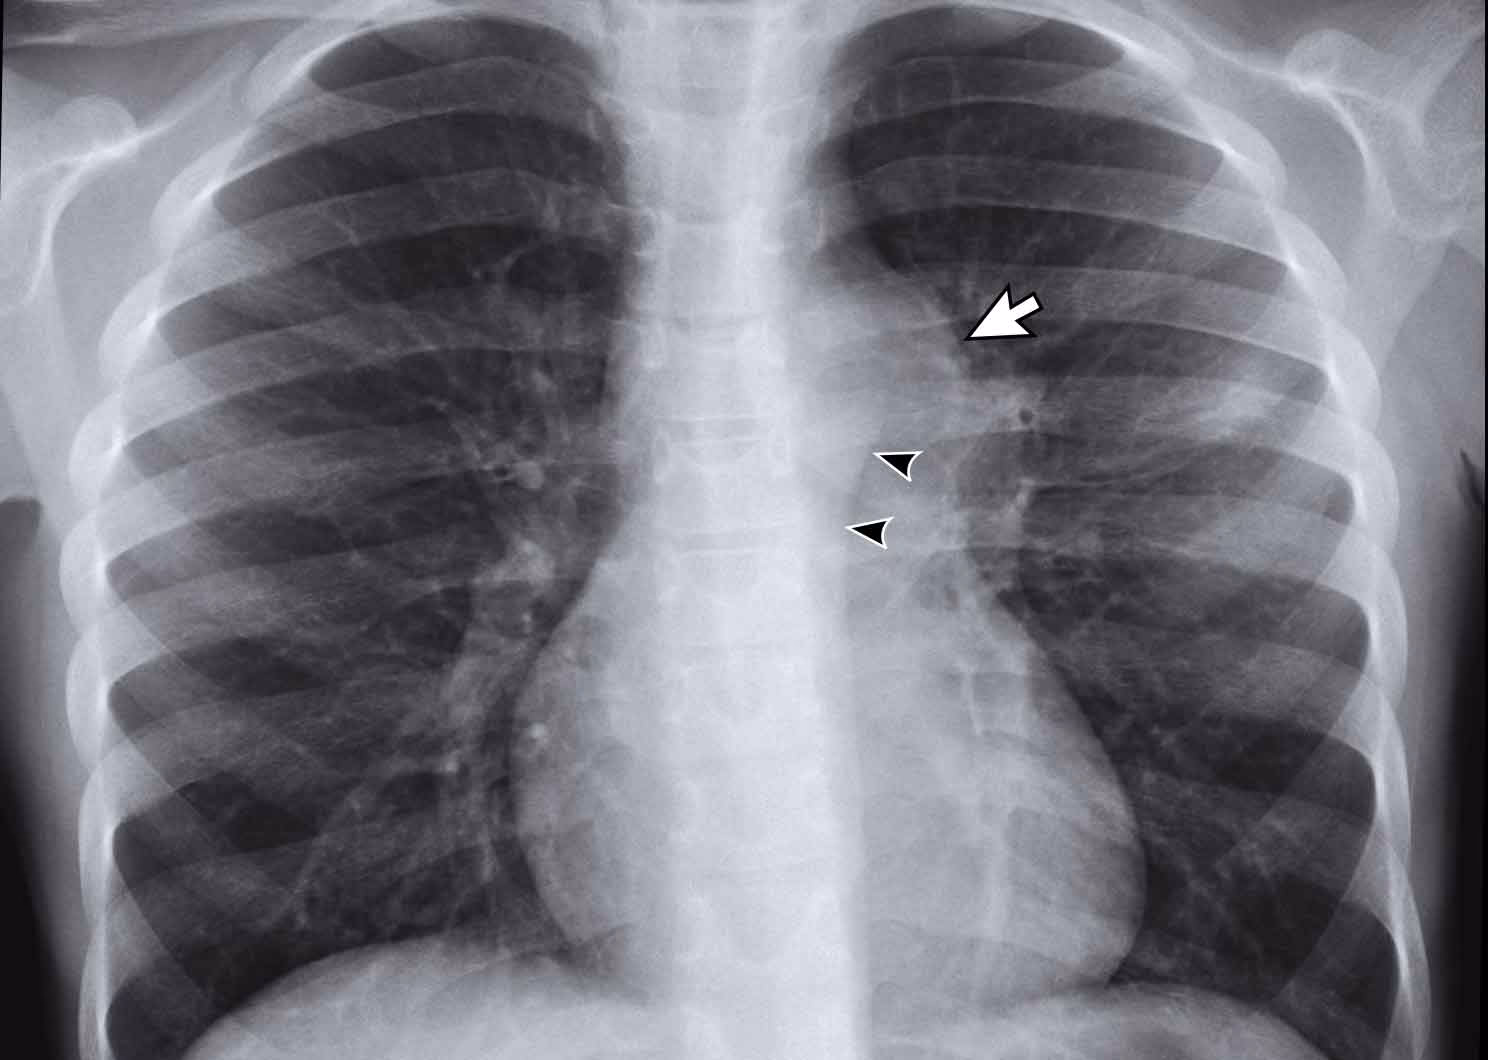

Når TB-infektionen er aktiv, reagerer kroppens immunforsvar, hvilket skaber inflammation og skader på lungevævet. Dette efterlader synlige spor på et røntgenbillede. De mest almindelige fund inkluderer:

- Infiltrater eller Konsolideringer: Dette er områder i lungen, hvor luftsækkene er fyldt med væske, celler og betændelsesmateriale, hvilket får dem til at fremstå som uklare eller hvide pletter på billedet. Ved aktiv TB ses disse ofte i de øverste dele (apikale segmenter) af lungerne.

- Kaviteter: Et af de mest klassiske tegn på fremskreden tuberkulose er dannelsen af kaviteter. Dette er bogstaveligt talt huller i lungevævet, der opstår, når det inficerede væv dør og hostes op. En kavitet ser ud som et mørkt, afrundet område omgivet af en tyk, hvid væg på røntgenbilledet. Kaviteter indeholder store mængder af TB-bakterier og gør patienten meget smitsom.

- Lymfeknudesvulst (Lymfadenopati): Forstørrede lymfeknuder i brystkassens midte (mediastinum) eller ved lungehovedårerne (hili) er et almindeligt tegn, især ved primær tuberkulose, som ofte ses hos børn og immunkompromitterede voksne.